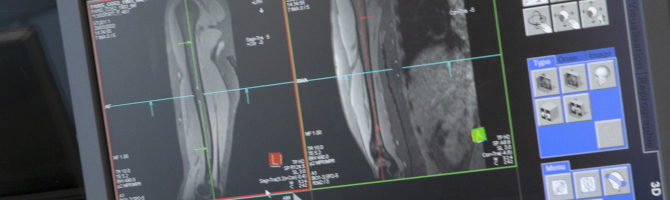

NMR and Spectroscopy Laboratory, headed by Harmen Reyngoudt, PhD & Benjamin Marty, PhD